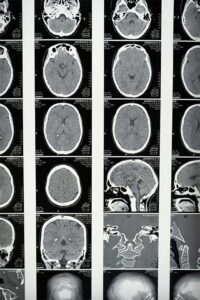

MPR/MIP in Medical Imaging and Their Implementation in XEUS: A Technical Guide

Introduction MPR/MIP workflows are foundational for extracting clinically actionable insight from volumetric imaging such as CT and MRI. MPR (Multiplanar Reconstruction) generates anatomically meaningful cross-sections